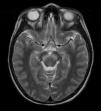

En la tabla 1 se muestran las principales características de nuestros pacientes. Todos presentaron fiebre de varios días de evolución al ingreso y una constelación de síntomas neurológicos que oscilaron entre decaimiento y somnolencia hasta inestabilidad, ataxia y temblor no intencional. A todos se les realizó punción lumbar, mostrando pleocitosis linfomononuclear en la citoquímica en 3 casos (1, 2 y 3). El análisis por reacción en cadena de la polimerasa (PCR) del líquido cefalorraquídeo (LCR), exudado respiratorio o heces detectó la presencia de EV en al menos, una de las muestras en los 4 casos. Solo en uno de ellos se detectó el virus en LCR, y en todos en la muestra fecal. En 3 de los 4 casos, la RM craneal mostró lesiones hiperintensas en romboencéfalo (fig. 1). Respecto al tratamiento, 2 pacientes recibieron corticoides, 2 de ellos inmunoglobulinas por vía intravenosa y uno solo recibió tratamiento sintomático. La evolución fue favorable en todos, estando asintomáticos al alta o con franca mejoría respecto al ingreso.

| 2 | Junio | 9 años | Fiebre 4 días Somnolencia Ataxia Nistagmo Pérdida de fuerza Vómitos | Heces Respiratoria LCR | Aumento de señal en T2 en mesencéfalo que se extiende a protuberancia, afectando a SG | IgIV 1g/kg/día, 2 días Metilprednisolona a 30mg/kg/día, 3 días | Mejoría No resolución |

| 3 | Septiembre | 22 meses | Fiebre 2 días Ataxia Vómitos Diarrea | Heces Respiratoria | Alteración de señal mostrada en T2 con hiperintensidad de SG bilateral de mesencéfalo | Metilprednisolona 2mg/kg/día, 5 días | Mejoría progresiva Resolución total de la clínica |

| 4 | Diciembre | 21 meses | Fiebre 5 días Somnolencia Ataxia Conjuntivitis | Heces | Hiperintensidad en T2 en bulbo y unión bulbo medular | IgIV 1g/kg/día, 2 días | Mejoría progresiva Resolución total de la clínica |

En el niño, la presencia de fiebre y afectación neurológica con compromiso del área romboencefálica (mioclonías, temblor y/o ataxia) y/o bulbar (afectación de pares craneales, trastorno de la deglución y del lenguaje, episodios de apnea y edema de pulmón neurogénico4 obliga al análisis del LCR, que suele mostrar pleocitosis linfocitaria y a la obtención de imágenes por RM en la fase aguda de la enfermedad, cuyos hallazgos típicos son la aparición de lesiones hiperintensas en T2, sobre todo en la protuberancia, la médula cervical, el mesencéfalo, los núcleos dentados y el hipotálamo5.